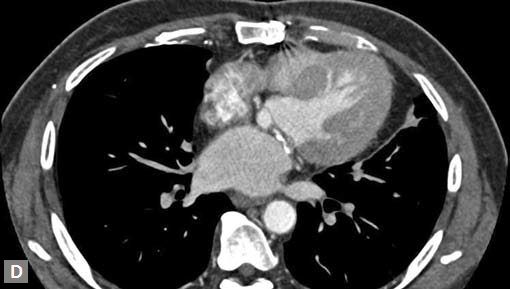

Filling defects (Figs 16A and B) may be seen in main

pulmonary artery (MPA), left pulmonary artery (LPA) and

right pulmonary artery (RPA), interlobar artery, segmental

divisions (Figs 17A and B). On occasions, detection in distal

parts of segmental divisions is difficult. This can be further

confounded by motion artifacts, non- or minimally opacified

accompanying pulmonary veins.